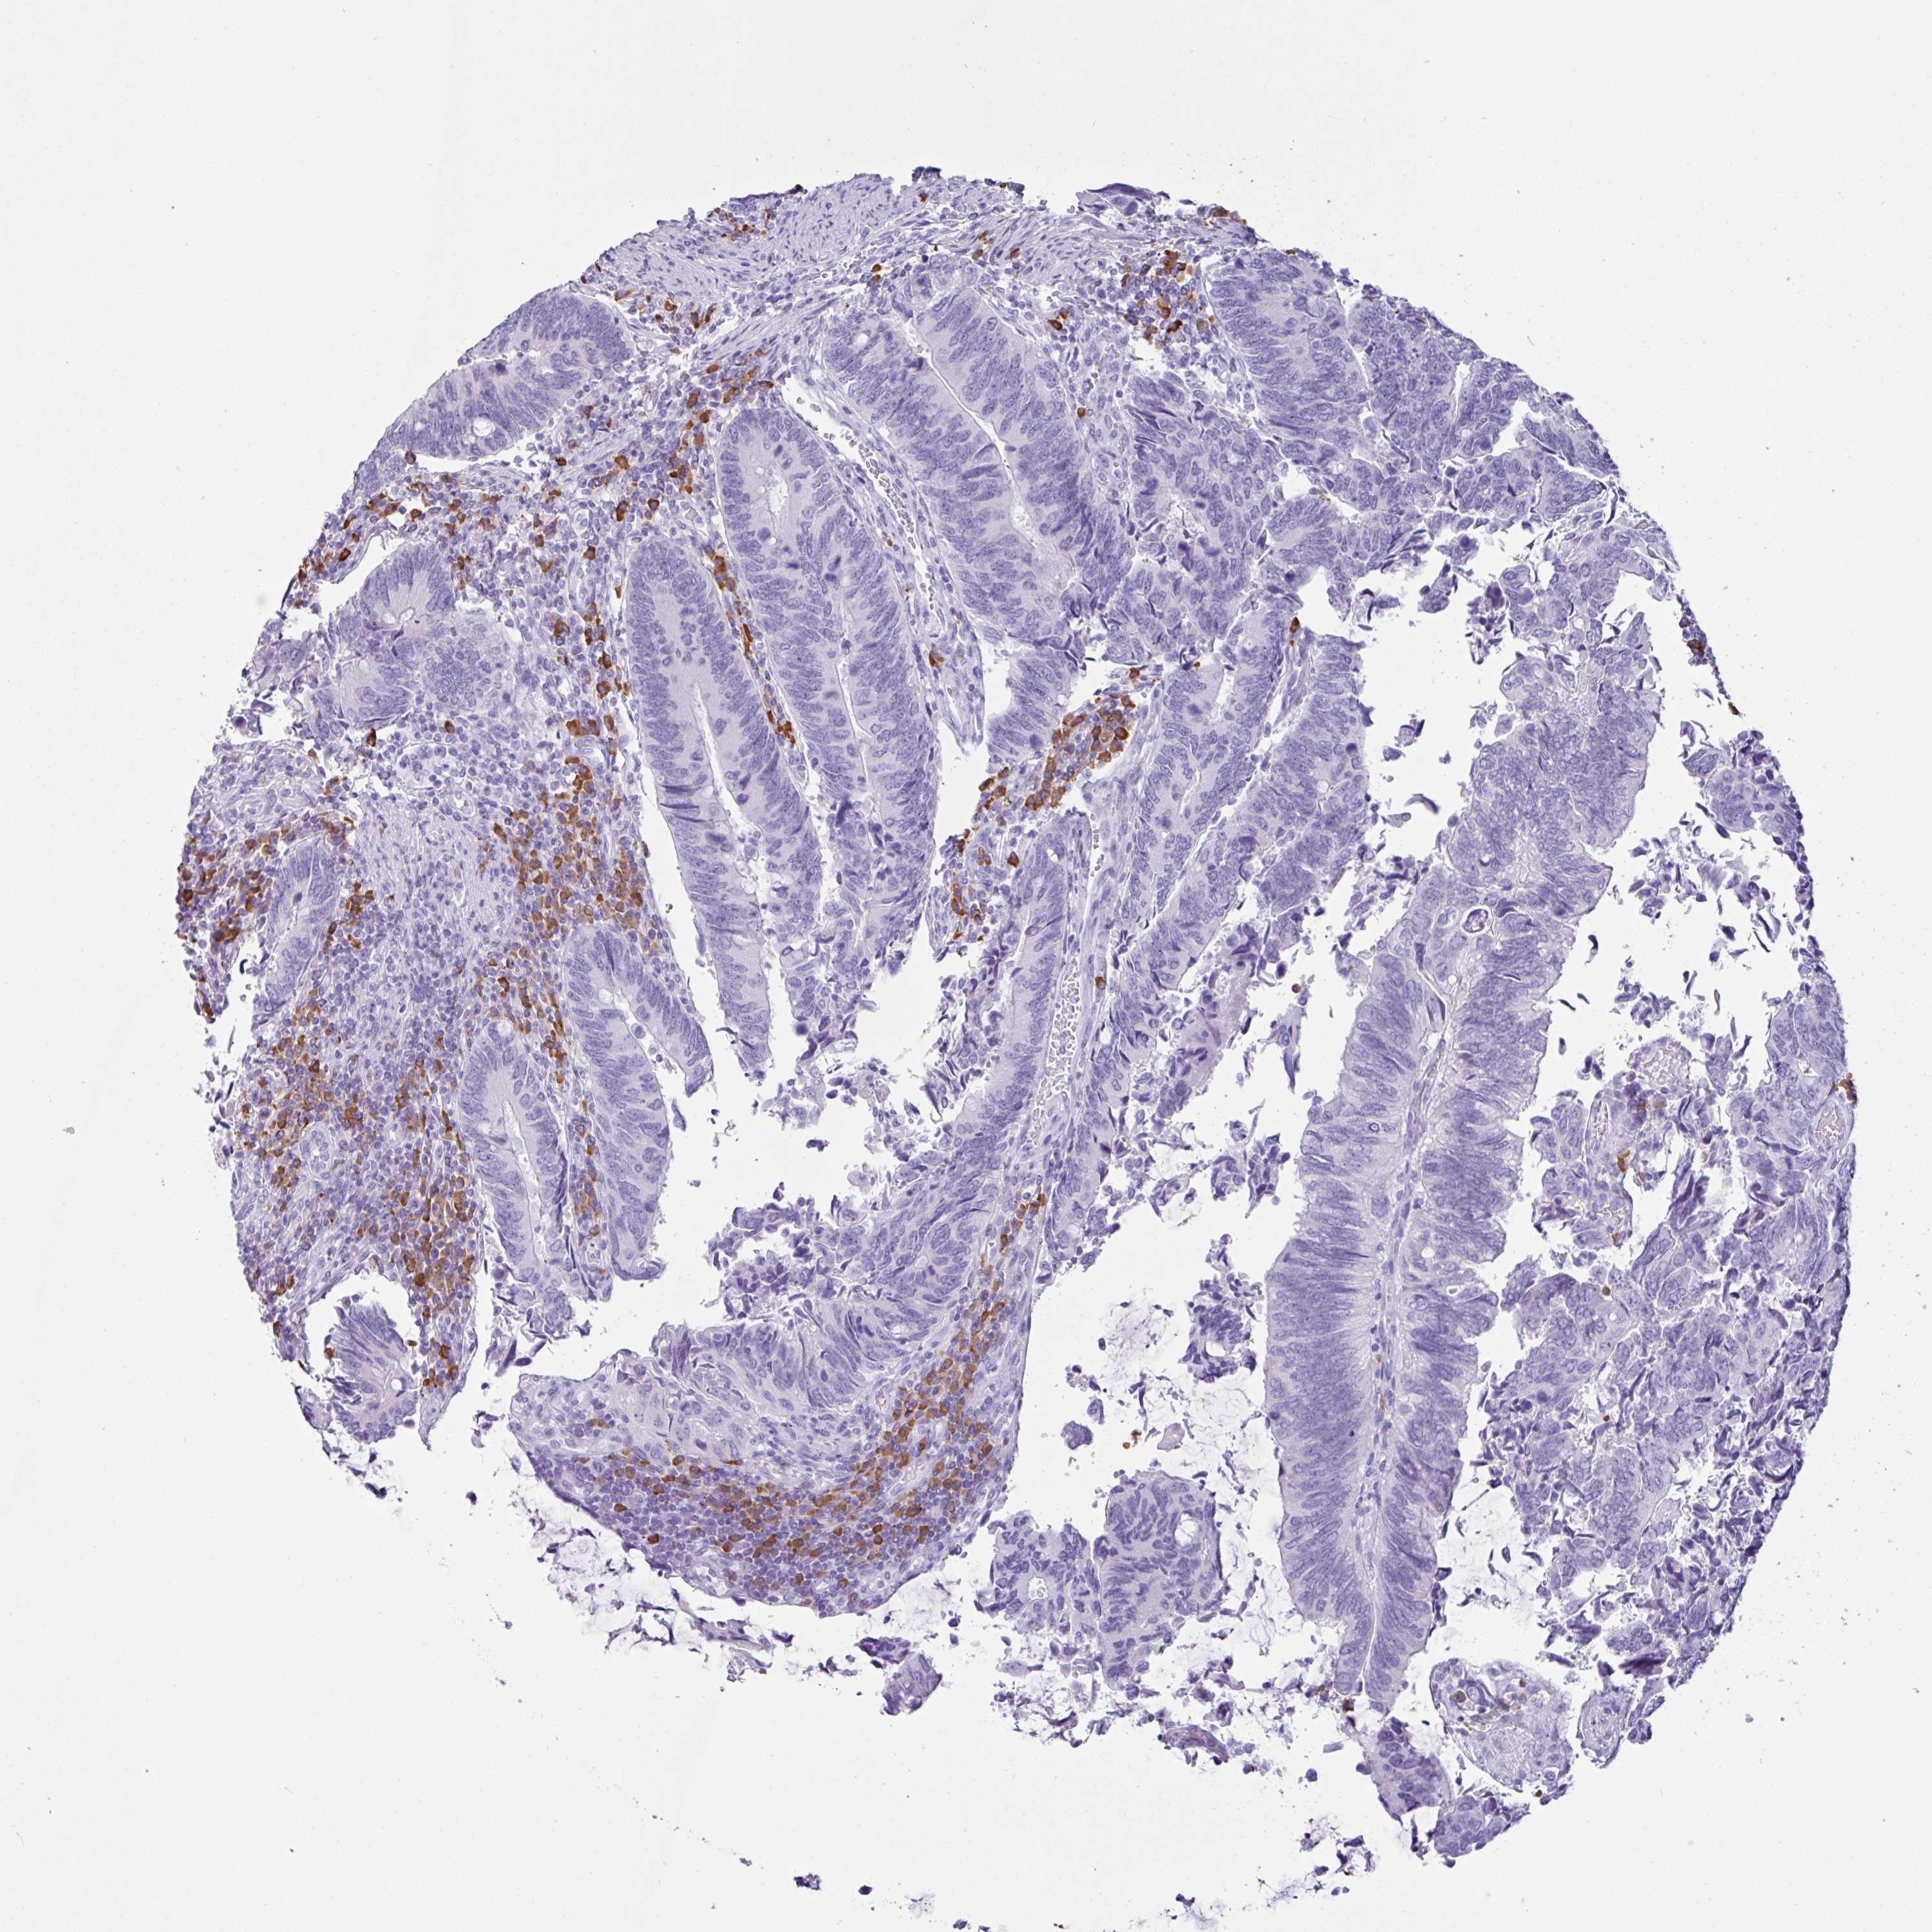

CANCER COLORECTAL CANCER Show tissue menu

Colorectal cancer

Human cancer

Colon adenocarcinoma

Rectum adenocarcinoma